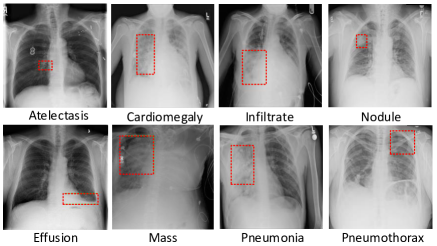

Since the last decade of years, as a promising technology, Medical Artificial Intelligence (Medical AI) has globally attracted interest. Especially after the emergence and fast progress of deep learning, a revolution of computer-aided diagnosis (CAD) technique has officially started and impacted in many bio-medical applications, e.g. diabetic eye disease diagnosis (Gulshan et al., 2016), cancer metastases detection and localization (Chen et al., 2015; Li and Huang, 2015; Liu et al., 2017), lung nodule detection (Setio et al., 2017), and survival analysis (Zhu et al., 2017), etc. However, introducing deep learning as solution to reading and understanding chest X-ray images is challenging due to the following reasons: 1) the visual patterns extracted from samples of different types of thoracic diseases are usually highly diverse in their appearance, sizes and locations (examples of common thoracic diseases in ChestX-ray14 dataset (Wang et al., 2017) are available in Fig.1) ; 2) retrieving massive high-quality annotations of disease, such as focal zone, on chest X-ray images is not affordable. The expenses result from both the cost of hiring experienced radiologists and the hardware requirements of collection, storage, processing of those data. Therefore, ChestX-ray14, although as the largest and most quality public chest X-rays dataset, does not provide with any pixel-wise annotations or coarse bounding boxes (example of which is in Fig.1) for most of chest X-ray images. Consequently, it is obvious that any machine learning models proposed to be compatible with ChestX-ray14 dataset are required to work merely with image-level class label plus a very small amount of bounding box annotations.

The problem of thoracic disease classification and detection on chest X-rays has been extensively explored. Recently, Wang et al. (Wang et al., 2017) released the largest chest X-ray dataset so far - ChestX-ray14, which collects 112,120 frontal-view chest X-ray images of 30,805 unique patients. Each radiography is labeled with one or multiple types of 14 common thorax diseases: Atelectasis, Cardiomegaly, Effusion, Infiltration, Mass, Nodule, Pneumonia, Pneumothorax, Consolidation, Edema, Emphysema, Fibrosis, Pleural Thickening and Hernia. These disease labels were mined from the associated radiological reports ( 90 % accuracy (Wang et al., 2017)). Besides, there are 880 X-rays provided with lesion regions annotated as bounding boxes by radiologists. In our experiments, we only used disease label as ground-truth in training and evaluating the model in disease classification. We also utilized the bounding boxes only for a visual evaluation of disease region localization on X-rays.